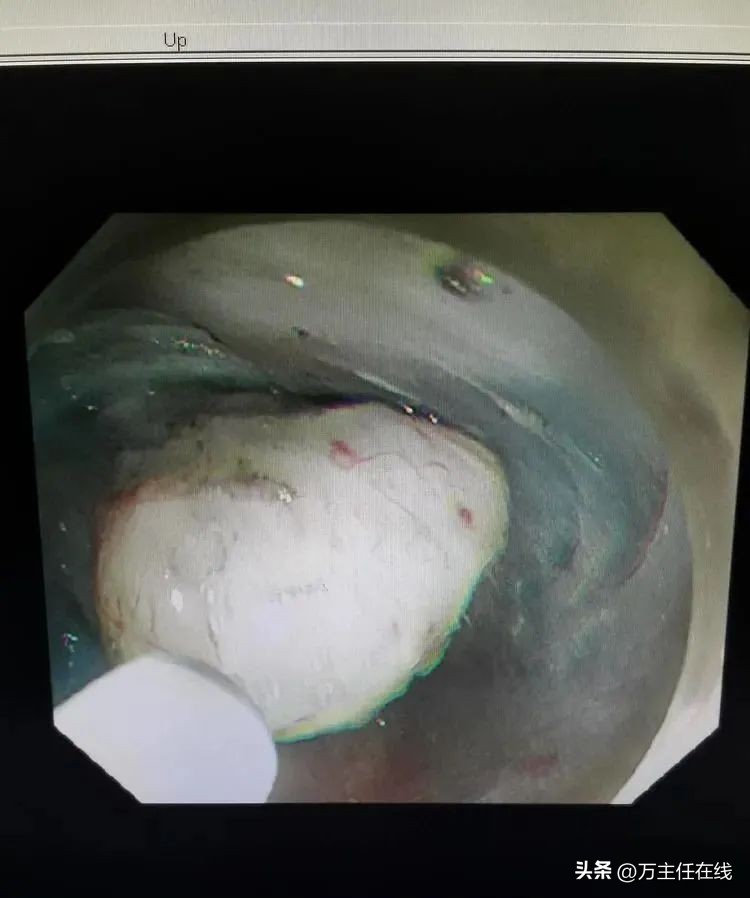

肿瘤显露近半

游离肿瘤大部

瘤体部分位于纵隔紧贴主动脉弓,即将完整剥除